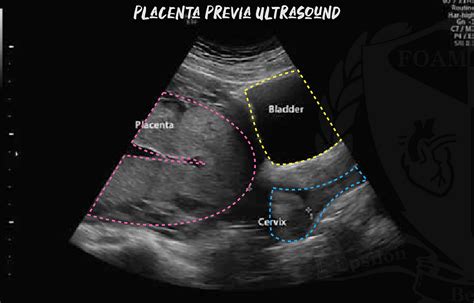

In alcune donne, la placenta si attacca in basso nell'utero e può coprire in parte o del tutto la cervice, ovvero il collo dell'utero. In molti casi, la placenta si sposta verso l'alto e si allontana man mano che l'utero cresce durante la gravidanza. Tuttavia, per alcune donne, la placenta continua a trovarsi nella parte inferiore dell'utero man mano che la gravidanza prosegue. In questa situazione, sussiste il rischio di sanguinamento vaginale, in particolare verso la fine della gravidanza, a causa della posizione bassa della placenta nell'utero.

Una placenta a impianto basso viene controllata durante l'ecografia di routine a 20 settimane di gravidanza (tipicamente tra 18+6 e 21+6 settimane di gestazione). L'ecografia ostetrica transaddominale di routine a metà gravidanza ha come uno dei suoi primi obiettivi la determinazione della posizione placentare. Un recente workshop multidisciplinare dell'American Institute of Ultrasound in Medicine suggerisce che il termine "placenta previa" sia usato quando la placenta si trova direttamente sopra l'orifizio uterino interno.

Se la placenta si trova in posizione bassa alla scansione delle 20 settimane, verrà offerta una scansione di follow-up a 32 settimane di gravidanza per vedere se è ancora in posizione bassa. Questa potrebbe includere una scansione ecografica transvaginale, dove la sonda viene delicatamente posizionata all'interno della vagina, poiché questo metodo è spesso più accurato nel determinare l'esatta relazione della placenta con la cervice.